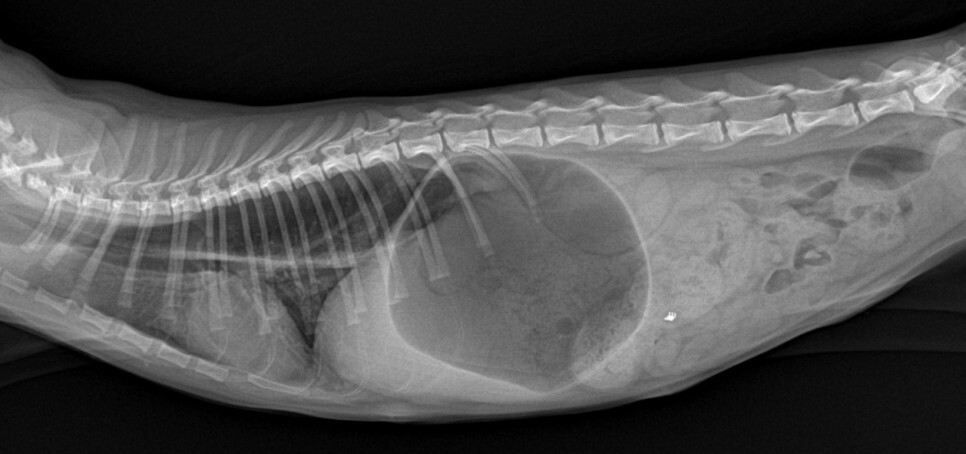

엑스레이 검사에서 식도가 확장되어 있고

위 내에 가스가 많이 차있는 것을 확인할 수

있었습니다. 복강 내 장에서는 이물질도 발

견이 되었습니다.